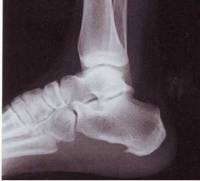

Tras la exploración, en la que encontramos dolorosa la presión en la tuberosidad calcánea (signo del salto calcáneo), y la revisión de las imágenes radiológicas decidimos realizar una infiltración con Triamcinolona y Bupivacaina en la inserción tendinosa que genero una gran mejoría, permaneciendo dos semanas asintomática. El dolor reapareció pero de menor intensidad, lo que le permitía una vida casi normal.

Se lo realizamos con éxito y obtuvimos una mejoría de casi ocho meses. Pero, María volvió al hospital un año después, la sintomatología era muy intensa y la imagen radiológica denotaba un gran avance del cuadro, María volvía esta vez a realizarse una cirugía sobre la fascia afectada, con una lesión agravada por el enorme sobrepeso.